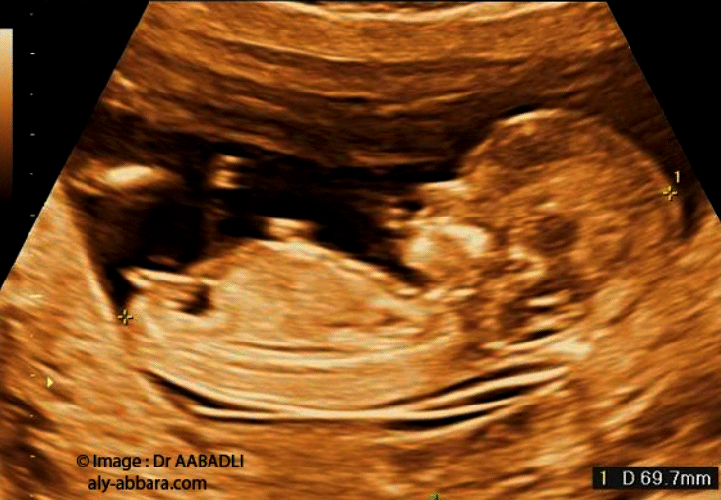

L'échographie de la clarté nucale est un test de dépistage qui permet d'évaluer le risque que votre bébé soit atteint du syndrome de Down (trisomie 21) BabyCenter Canada BabyCenter Canad ;468 Down syndrome) », Prenat Diagn, vol 30, no 1, 10, p 5764 (PMIDSpé chir et gynécoobst, s21DP 34,02 EUR Spé chir et gynécoobst, s21DP OPTAM 37,05 EUR Spé chir et gynécoobst, non conventionné 34,02 EUR Il s'agit de la choriocentèse, qui consiste à prélever un très petit fragment du placenta (villosités) Ce geste est réalisé entre 10 et 12 semaines d' aménorrhée , en cas de fort

Clarté nucale prix La clarté nucale est donc tjrs mesurée entre 35 et 39mmTout le reste est tjrs tout à fait normal Je n aurai pas de biopsie car je suis sous aspegic et qu avec mes antécédent de fc, le ratio beneficerique est pour eux important Ventriculomégalie et kystes plexus choroïdes J'ai fait l'échographie morphologique vendredi matin dernier et il en est ressorti que les ventricules cérébraux de mon papoute sont plus gros que la moyenne (moyenne ne devrait pas dépasser 10mm et moi j'en suis à 10,5mm) De plus, ils ont décelé des kystes sur les plexus choroïdesLe fœtus continue doucement sa grossesse et atteint en cette vingtetunième semaine de grossesse, la taille de 24 cm pour environ 450 grammes Faisons le point sur cette 19ème semaine d'aménorrhée 19ème semaine de grossesse pour la maman 19 SG/21SA, le ventre commence